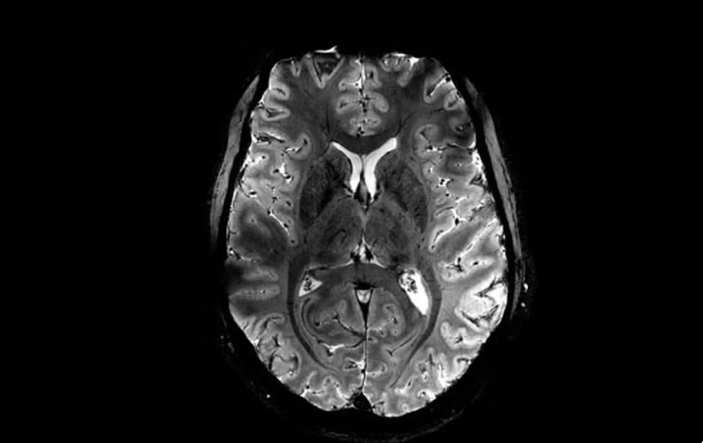

Imagem do Iseult com um campo magnético de 11,7 teslas. — Foto: Reprodução/Comissão de Energia Atômica da França (CEA)

A Comissão de Energia Atômica da França (CEA) divulgou nesta terça-feira (2) as primeiras imagens do cérebro humano feitas pelo aparelho de ressonância magnética mais potente do mundo. De acordo com os responsáveis pelo projeto, o scanner atingiu um nível de precisão jamais visto, algo que pode ser decisivo para detectar doenças.

O campo magnético criado pelo scanner é de 11,7 teslas. Essa potência permite que a máquina escaneie imagens 10 vezes mais precisas do que os aparelhos normalmente utilizados em hospitais – cuja potência geralmente não supera os três teslas.

Em uma tela de computador, Vignaud comparou imagens tiradas por esse poderoso scanner, apelidado de Iseult, com imagens de uma ressonância magnética normal.

“Com essa máquina podemos ver os pequenos vasos que alimentam o córtex cerebral, ou detalhes do cérebro que eram quase invisíveis até agora”, detalha.